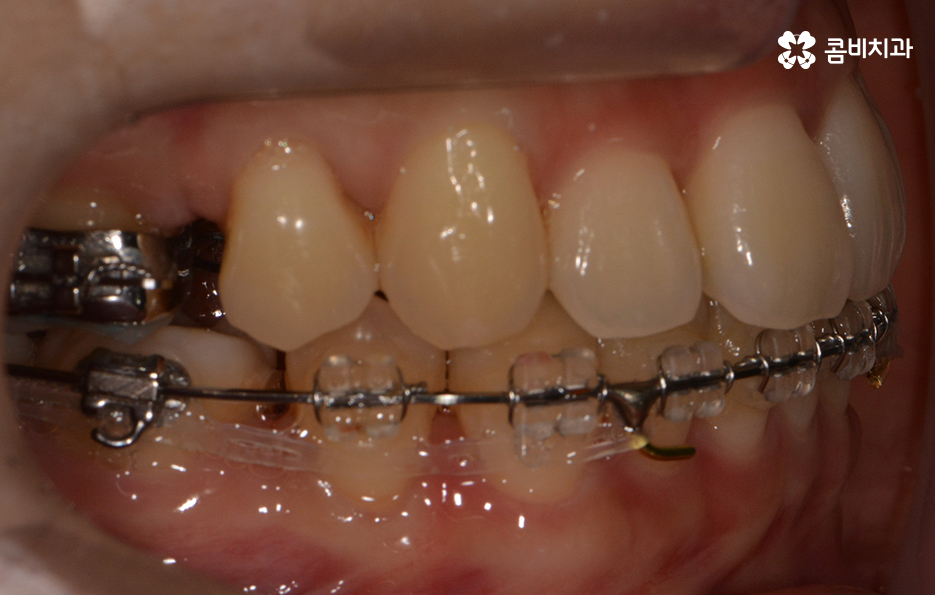

발치가 진행되었고 콤비교정 장치를 사용하여 교정이 진행된 사례

외부에 교정 사실을 되도록 알리지 않고 싶을 때

콤비교정을 통해서 치료가 진행되는 경우가 많습니다.

콤비교정은 윗니는 설측으로 장치가 부착되며 아랫니는 순측으로

치아 바깥쪽에 장치가 부착되는데요.

평상시 대화를 하고 웃을 때 윗니가 위주로 보이기 때문에

크게 웃지 않는 이상 일상생활을 하실 때

교정 사실이 거의 드러나지 않을 정도로 높은 심미성을 갖고 있습니다.